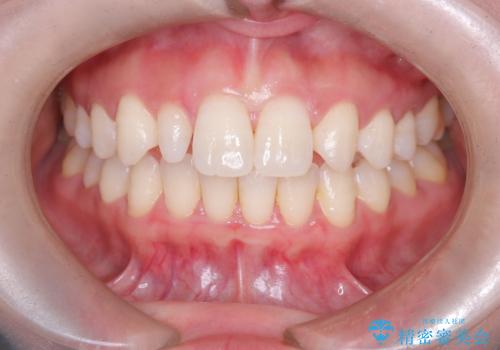

- 「前歯の見た目が気になる」を主訴に来院された患者様です。

右上2が矮小歯だったので、オールセラミッククラウンで審美修復しました。

見た目が改善され、大変ご満足いただけました。